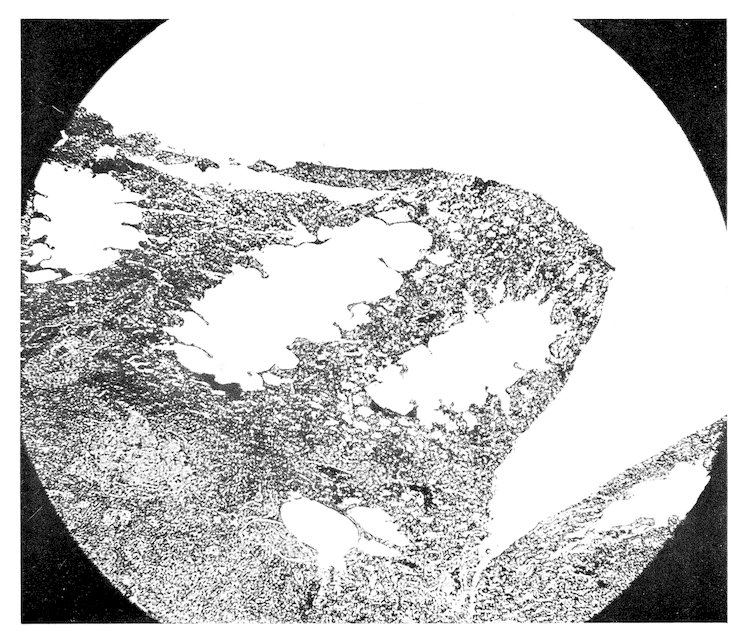

Some attention has been given to the study of diets for the wild specimens of our Garden, but no systematic observations have been made or records kept upon purely physiological subjects. Reference will be made at appropriate places to accepted comparative physiological facts, but our statistics permit additions to such knowledge only in a limited manner and in isolated instances. Doctor Corson-White has very ably summarized the diet, alimentary tract and physiology of the zoological groups with the pathology as found in our records.

A word might be added here as to the destruction of animals by injury from fighting and harassment by others in the cage. Fighting doubtless causes death, especially when males are together, but it is our experience that in cases of traumatic death search should always be made to see if the resistance of the dead animal had not been reduced by some disease. This is well illustrated in birds. Very frequently a specimen will come to autopsy with its head feathers plucked out, or with a billthrust in the wing or pelvic region. Such birds are not infrequently suffering from malaria, or heavy intestinal parasitism or from organic disease whereby the resistance and self-preservatory power has been decreased.

The foregoing survey of the approach to our subject reveals the multiplicity of factors which affect the study of comparative pathology. No one of them can be entirely omitted, no one is without some effect upon the origin and expression of disease, and no one is fully understood. Yet it is to be hoped that a study of our material, accumulated under routine conditions and uninfluenced by any experimental procedures, will demonstrate the natural response of various zoological groups to morbific agencies. Perhaps reactively some of the modifying 41conditions may thus be understood. It is also not unreasonable to expect that alterations observed as natural responses in a large number of specimens in nearly normal surroundings would serve as more reliable guides to investigative speculation than would changes in a few animals under artificial technical experimentation. We hope that the few facts we have been able to record may afford someone a basis for further biological studies. It is also to be hoped that something has been learned which in the end will afford an explanation of the diseases of man. Too great optimism in this direction should be guarded against because the human being is indeed an animal sui generis and, from the standpoint of normal conditions of nature, a wild animal.

The zoological classification found on pages 43–46 was compiled in 1903 by Dr. A. E. Brown on the basis of the British System. With a few exceptions the computations in the text are made on the basis of zoological orders since the number of specimens in families is often too small and the complications of so many different figures would be confusing. The tables will be found to correspond to the sequence of the classification. Dr. Corson-White has, however, used for her analysis the dietary groupings. A carnivore in her chapter implies strictly a meat-eater, in the rest of the book one of the zoological group Carnivora.